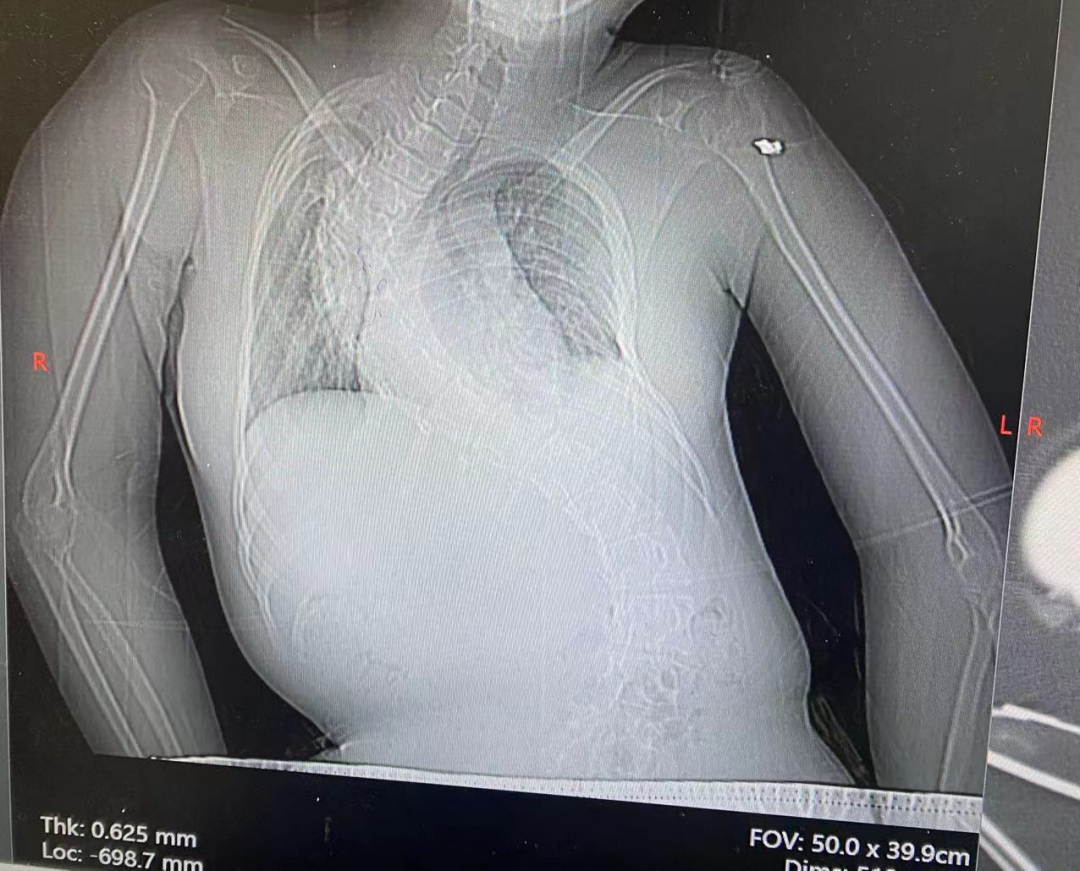

检查结果进一步揭开了病情的严重程度:12 月 26 日胸部 DR 提示支气管肺炎、脊柱 S 型侧弯;12 月 30 日胸部 CT 更是显示右肺支气管闭塞伴右全肺不张、左肺下叶炎症、右侧胸腔积液,头颅 CT 还发现了鼻窦炎。多重并发症叠加,让这个本就患有重症肌无力的孩子,陷入了多脏器功能受威胁的险境。

在医护团队的全力守护下,小西的病情逐渐好转:1 月 5 日复查胸部 CT 显示,两肺炎症较之前明显吸收,右肺也成功复张;心率、血氧、血压等生命体征趋于平稳,不再发热。经过十余天的紧张救治,小西终于达到临床治愈标准,目前已顺利出院。